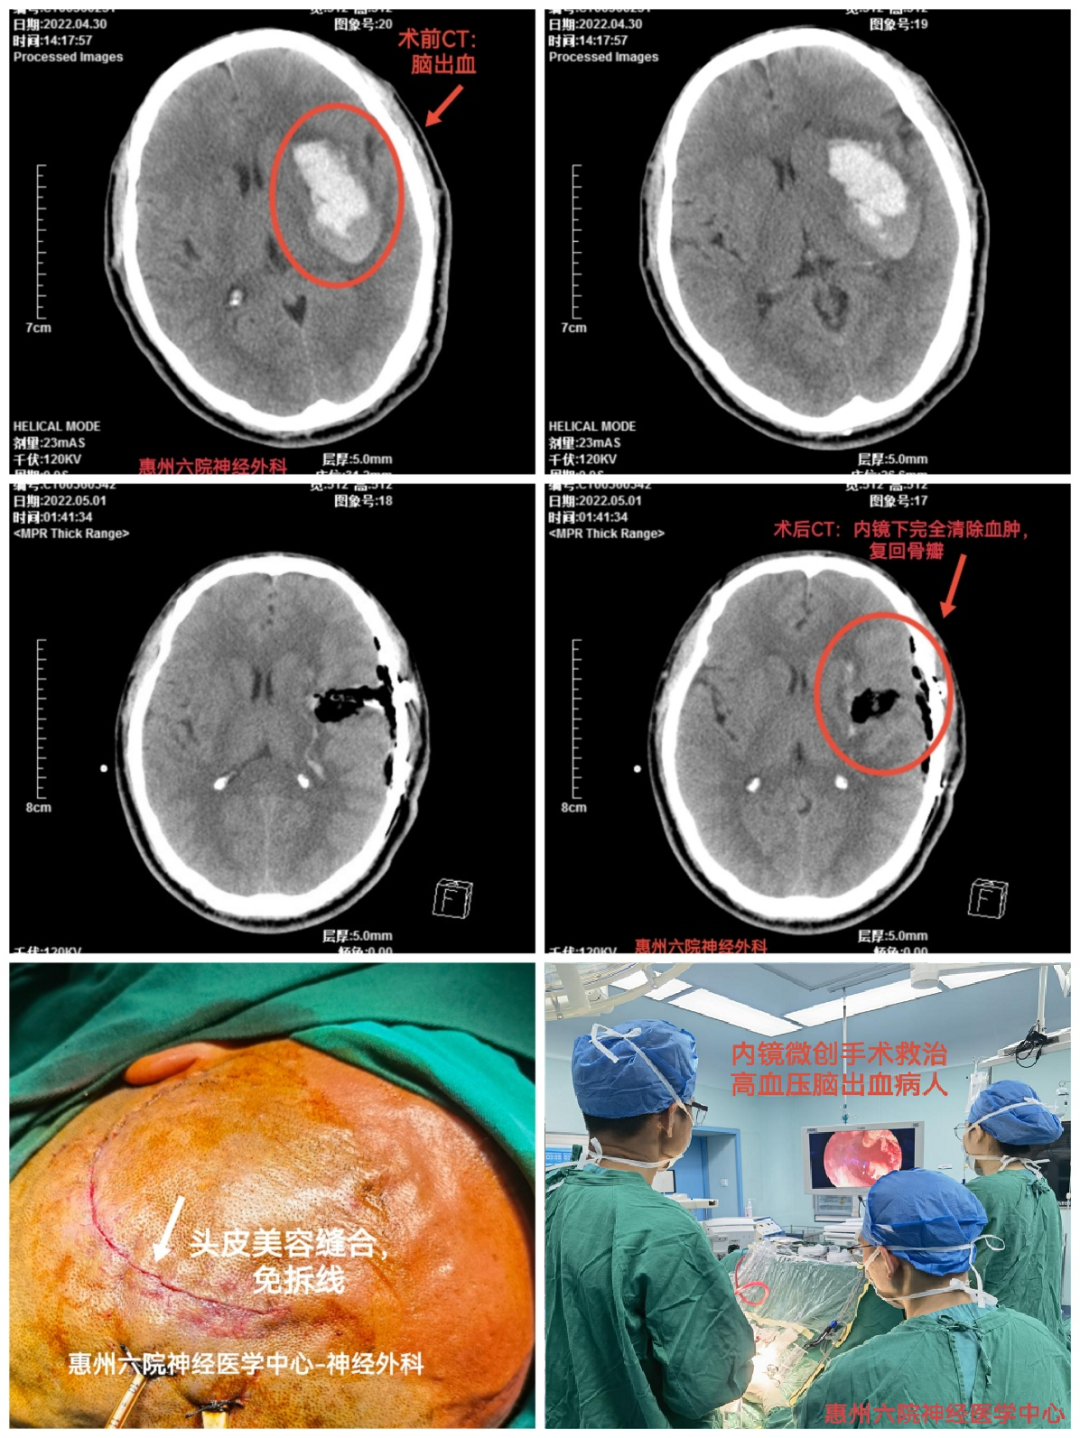

腦出血是我國(guó)居民死亡和殘疾的主要原因之一,具有高緻殘率、高死亡率、經(jīng)濟負擔重等特點,是影響群衆健康的重大疾病。以往多采用骨瓣開(kāi)顱清除血腫的辦法,創傷大、并發(fā)症多。

從2020年開(kāi)始,惠州市第六人民醫院神經(jīng)外科應用新技術——“神經(jīng)内鏡小骨窗球囊通道(dào)微創手術治療腦出血”,迅速提高腦出血的救治水平。

該項新技術,系采用小骨窗球囊通道(dào)微創方法進(jìn)入腦内血腫,在神經(jīng)内鏡輔助下清除腦内血腫。微創手術損傷小、耗時(shí)短、并發(fā)症少、成(chéng)功率高。至今已成(chéng)功開(kāi)展60多例,取得了良好(hǎo)的社會(huì)效益。